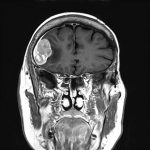

625

'25年4月

60代

円蓋部髄膜腫

頭蓋内腫瘍摘出術

No.’25_27 手術前1

No.’25_27 手術前2

No.’25_27 摘出 前

No.’25_27  摘出 中

No.’25_27 摘出 後